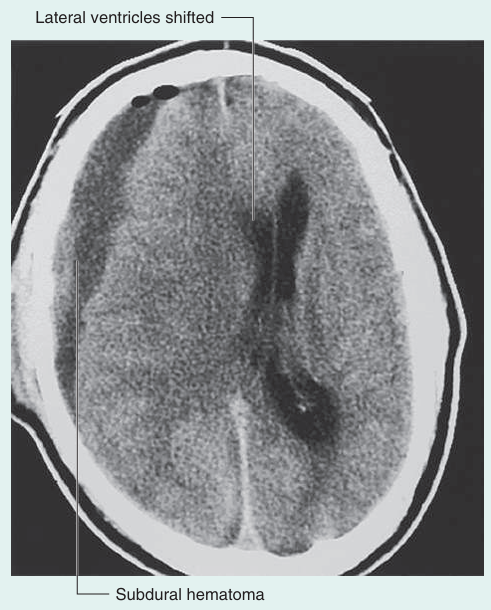

1) 경막바깥출혈, 경막밑출혈: 주로 외상과 관련

분류

출혈 발생 위치

주된 발생 원인

특징

영상

경막외혈종

두개골과 경막 사이

두개골 골절

주로 압력 높은 arterial 혈종

경막이 혈종의 압력을 막는 방패 역할을 하면서 뇌실질은 거의 손상되지 않고, 예후가 좋다.

렌즈 모양 출혈

경막하혈종

경막과 거미막 사이

뇌와 두개골을 연결하는 혈관이 끊어지는 경우

주로 압력 낮은 venous 혈종

경막 안쪽에 혈종이 생겨 머리 전체에 피가 고일 수 있다. 뇌실질이 직접 눌려 예후가 좋지 않다.

초승달 모양 출혈